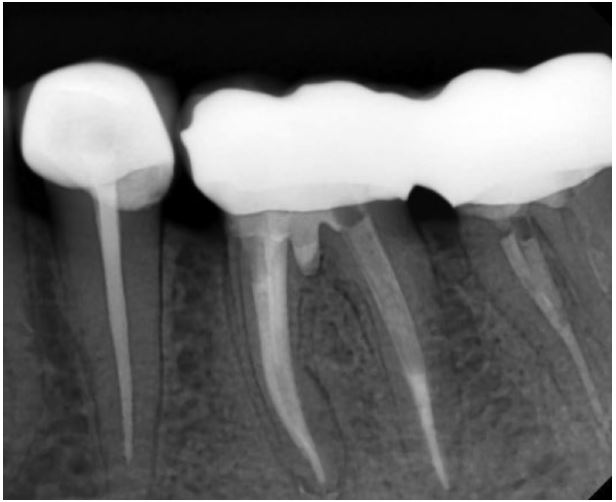

Trong thời gian theo dõi 1 năm thì bệnh nhân không có triệu chứng. Phim X quang cho thấy sự lành thương và thu nhỏ kích thước khối thấu quang vùng chẽ.

Hình 13.12. X quang sau 1 năm.